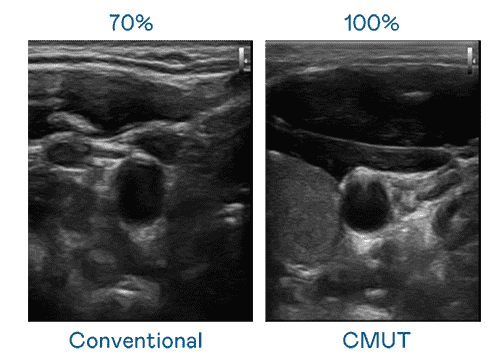

CMUT 技术是一种用电容式微机电元件来产生超音波讯号的技术。。。。与传统 PZT 压电式技术相比,,,,CMUT 频宽增加 30%,,更宽频的超音波讯号让影像解析度大幅提升,,是实现高影像品质医疗超音波扫描、、、、促进精准医疗发展的关键技术。。。

大频宽带来超清晰影像

超音波影像的解析度高低,,,,首先取决于探头能发出的讯号频宽。。。。EBpay CMUT 可提供高清晰的超音波讯号,,,,提供高频宽、、、、高灵敏度、、影像纹理细节更高的超音波影像,,,,协助医护人员缩短影像判读时间及利用精准的医疗影像进行诊断。。。